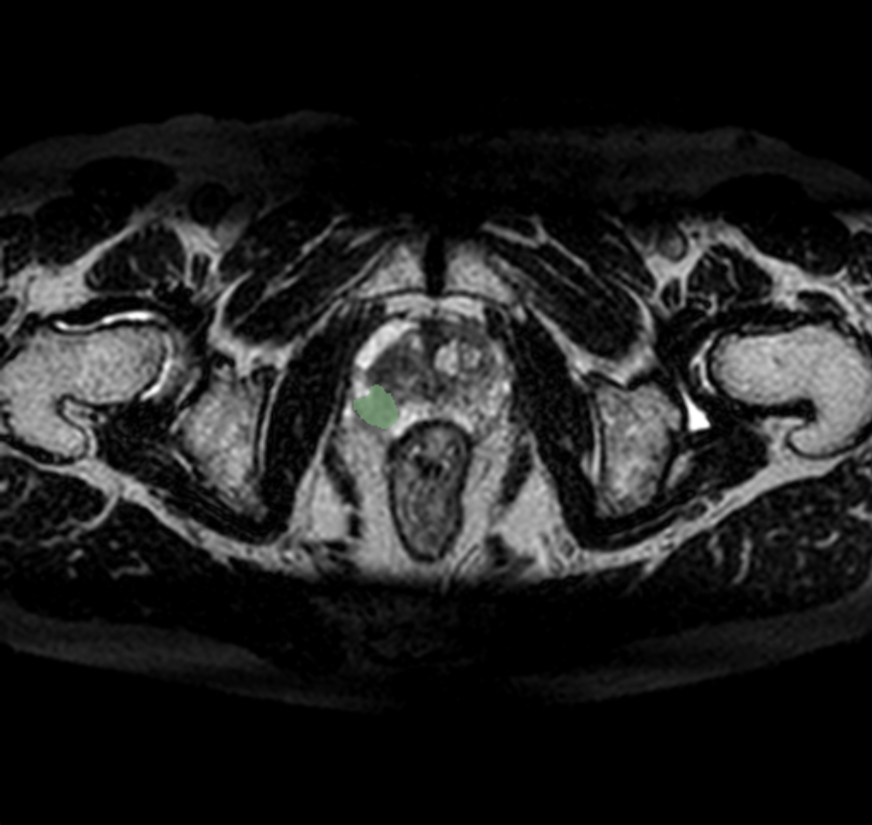

Callisto DataHub 2周年を記念し、専門医が作成した病変BBox付きの肺がん疑いX線データセット 50症例と、病変セグメンテーション付きの前立腺がんMRIデータセット(PI-RADS 4・5) 50症例を無料配布しています。前立腺がんMRIデータセットには、T1w, T2w, DWI, ADC, (あれば)DCEが含まれます。いずれも日本の医療施設由来で、所見文付き・商用利用可能なデータセットです。

前立腺がんMRIデータセット